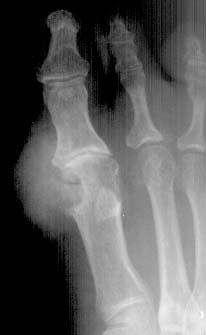

痛风性关节炎:尿酸代谢障碍,血尿酸增高,男性多见。;临床表现:潜伏期;急性发作期(1/3有X线改变);慢性期.;病理:滑膜增厚,肉芽组织,痛风结节

初期:关节肿胀,四肢关节均可,以第一跖趾关节为著.

晚期:关节骨端骨侵蚀性破坏,呈穿凿样,边界清楚。关节软骨破坏发生较晚,间隙变窄。关节旁或软组织内有痛风结节(可钙化)。

侵蚀性骨破坏

痛风结节